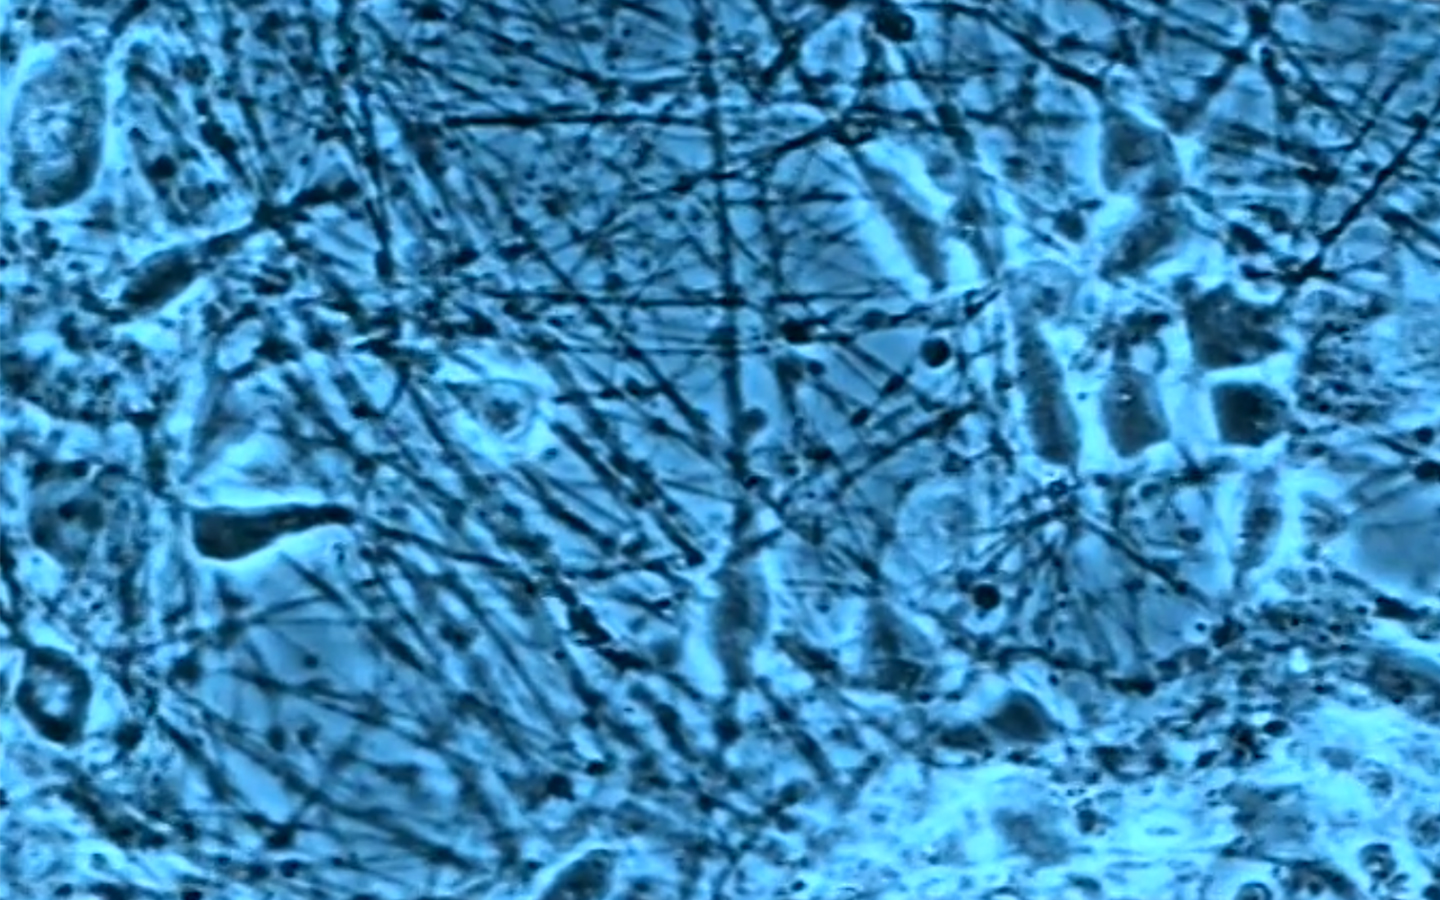

It is at the crossroads of two paths: that of director of films relating to science, and a doctorate in History and Philosophy of Science that my activities lie. I am interested in representations, figures and images produced by science, and their circulation outside the scientific and medical field.